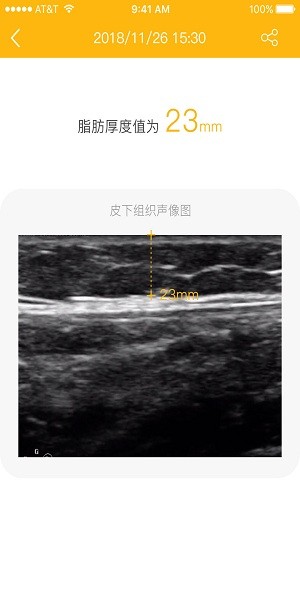

脂肪厚度儀軟件與設(shè)備連接完成后使用者就能在app中實時看到設(shè)備檢測后的數(shù)據(jù),通過清晰的聲像圖來得到對應(yīng)的脂肪厚度,圖標概括分析更加清晰明了,具體功能有需要的用戶可以來下載了解更多。

“脂肪厚度儀APP”是“脂肪厚度儀”產(chǎn)品Z1的配套APP,“脂肪厚度儀”Z1是一款超聲波原理的可以快速測量人體皮下脂肪厚度的智能設(shè)備,可以幫助肥胖人群、健身人群、愛美女性、糖尿病人群等長期監(jiān)測皮下脂肪厚度變化。